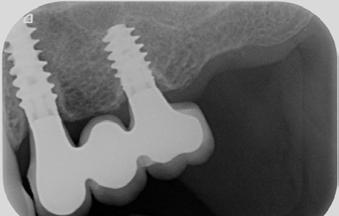

Prof. Curd Bollen, prof. Martin Jörgens (Hollandia)

EGY- ÉS KÉTRÉSZES KERÁMIA-

IMPLANTÁTUMOK A FOGÁSZATBAN

Korábban a cirkonimplantátumok egyrészes (egyfázisú) kialakításban voltak csak elérhetők. Ma már azonban léteznek kétrészesek (kétfázisú, ún. hibrid-koncepció) is, amelyeket széles körben használnak a hiányzó fogak pótlására.

Cikkünk az egy- és kétrészes kerámiaimplantátumok előnyeit és hátrányait klinikai, tudományos, valamint páciensközpontú szempontok alapján hasonlítja össze.

Az egy- és kétrészes implantátumok közötti különbségeket, előnyeiket, valamint hátrányaikat nyolc vizsgálati szempont mentén mutatjuk be.

1. Kialakítás

Az egyrészes rendszereknél az implantátum és a fej egy egységet képeznek, így nincs bakteriális szivárgás, ellenben a kétrészes implantátumokkal, ahol az illesztés mentén mindig van egy minimális rés.17 Természetesen ez azt is jelenti, hogy az egyrészes implantátumokon a felépítmény (ideiglenes és végleges egyaránt) csak cementtel rögzíthető. Többféle ilyen implantátum is van forgalomban (2. táblázat).

Az ennél összetettebb, kétrészes implantátumok kettő vagy három darabból épülnek fel: magából az implantátumból, a protetikai fejből és a fejet rögzítő átmenőcsavarból. Amenynyiben a fej cementtel rögzül az implantátumban, nincs átmenőcsavar. A csavar készülhet titánból, aranyból, karbonból vagy cirkóniumból (2. ábra).

A kétrészes rendszerek közt több olyan is van, amely belső kapcsolatos, ezeknek azonban eltérő a stabilitásuk (4. ábra).

Az implantológiában mára az egyrészes és kétrészes implantátumokkal hasonló prognózist lehet elérni. A legfrissebb kutatások egyértelműen azt mutatják, hogy kiváló klinikai eredmények érhetők el az egy- és kétrészes kerámiaimplantátumokkal is. Viszont a kétrészes kerámiaimplantátumok esetében még nem áll rendelkezésre elegendő hosszú távú tudományos adat, amely alátámasztaná mindennapi használatukat. Ezért kiemelten fontos, hogy ilyen implantátumok beültetése előtt a pácienst teljeskörűen tájékoztassuk, és ezt követően egyezzen csak bele a kezelésbe.